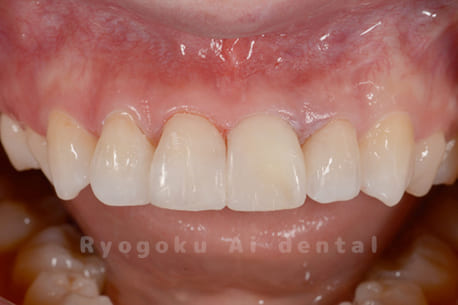

Case02

- 原因

- 歯の神経が死んでしまったことによる変色

- 治療内容

- 根管治療+ブリーチング+ダイレクトボンディング

- 治療費用

- 198,000円

上顎前歯部の歯の神経が死んでしまったことによる1歯の変色と歯のすきっ歯を根管治療、ブリーチング、ダイレクトボンディングで改善したケースです。